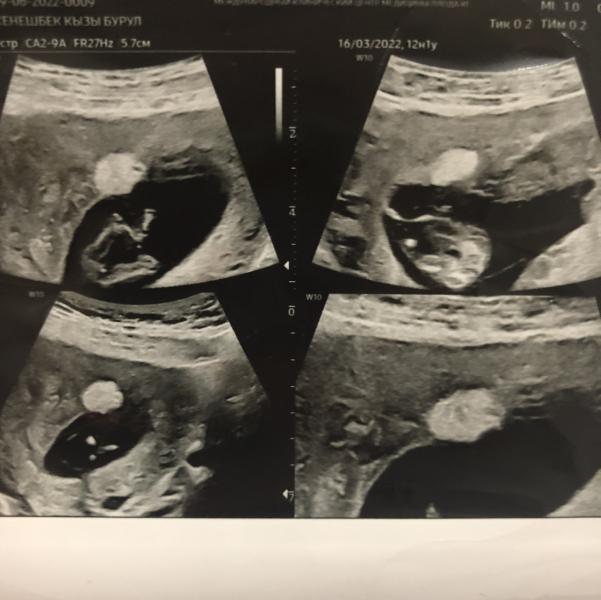

Первый скрин просто на память😊

У меня в матке какое то образование нашёл Арапов, до скрининга раз 4 была на узи и никто не увидел этого.

Говорит что точно не знает что это и даже пока предположить не может, спрашивал были ли жалобы или выделения кровянистые, но ничего такого не было, иногда тянул живот и если резко вставала то покалывало бок, будем наблюдать по...